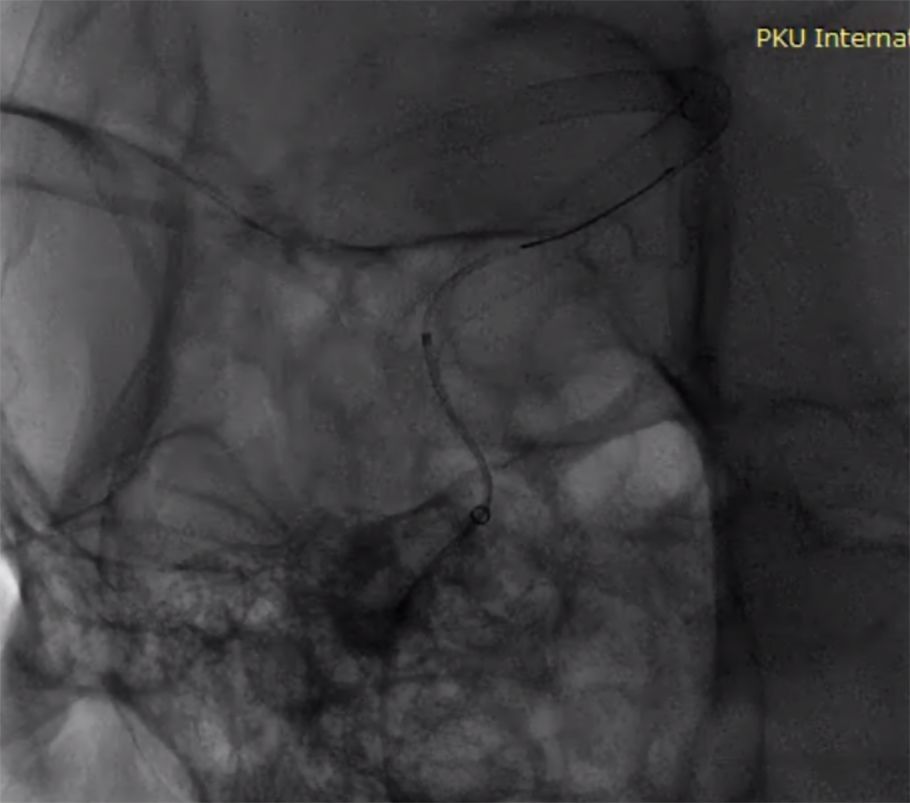

术前造影:

(1)右侧颈内动脉海绵窦段至颈内动脉末端巨大夹层动脉瘤伴血栓形成(图1)。

图1